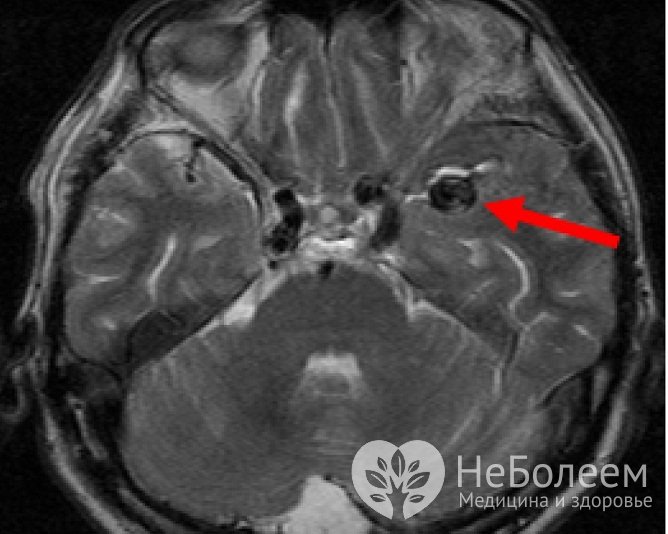

Аневризма сосудов головного мозга на МРТОбнаружение крови в цереброспинальной жидкости, полученной в ходе люмбальной пункции, – подтверждение разрыва аневризмы сосудов головного мозга.